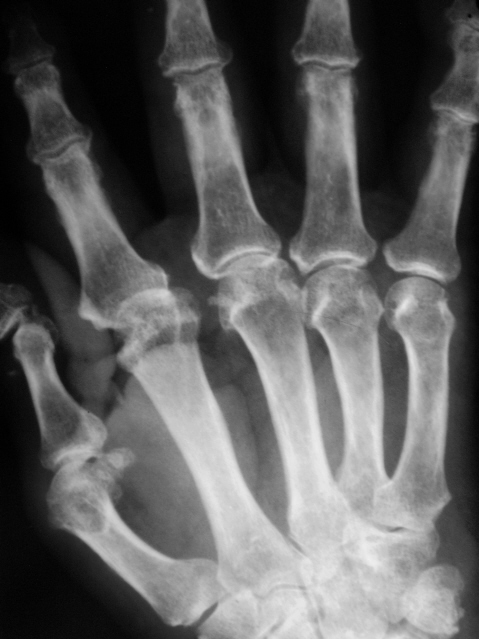

Катенёв Валенти... Дата публикации 03.07.2009, 23:53 Пациент направлен в рентгеновский кабинет "для рентгенографии кистей" терапевтом с диагнозом "Ревматоидный артрит". Произведены рентгенограммы. Ваше мнение коллеги? Сб, 04/07/2009 - 00:59 #1 Петрович Не на сайте Был на сайте: 7 лет 2 месяцев назад Зарегистрирован: 22.03.2009 - 01:13 Публикации: 3908 Для полноценной диагностики "Ревматоидного артрита" маловато представлено костей запястья. А из того, что представлено видна Подагра. Или нет? Неоднозначно всё Сб, 04/07/2009 - 12:12 #2 Ермолаев Не на сайте Был на сайте: 8 лет 10 месяцев назад Зарегистрирован: 07.02.2009 - 16:33 Публикации: 670 Соглашусь с мнением Петровича! Больше похоже на подагрический артрит. dok Вс, 05/07/2009 - 01:12 #3 OPEXOB Не на сайте Был на сайте: 9 лет 11 месяцев назад Зарегистрирован: 26.07.2008 - 10:02 Публикации: 280 Господа, мнения разделились. Поясните, кто что видит, а не окончательный диагноз. Подагра? где тофусы, "пробойники". Вс, 05/07/2009 - 12:31 #4 Ермолаев Не на сайте Был на сайте: 8 лет 10 месяцев назад Зарегистрирован: 07.02.2009 - 16:33 Публикации: 670 Коллега Орехов! Мнения, как раз и не разделились, а сошлись в одном - подагра. dok Вс, 05/07/2009 - 15:50 #5 alexey.krasnov Не на сайте Был на сайте: 10 лет 3 месяцев назад Зарегистрирован: 19.05.2009 - 10:52 Публикации: 30 Абсолютно согласен с Др. Ермолаевым и остальными. Bis Dat Qui Cito Dat

Для полноценной диагностики "Ревматоидного артрита" маловато представлено костей запястья. А из того, что представлено видна Подагра. Или нет?

Соглашусь с мнением Петровича! Больше похоже на подагрический артрит.

Коллега Орехов! Мнения, как раз и не разделились, а сошлись в одном - подагра.